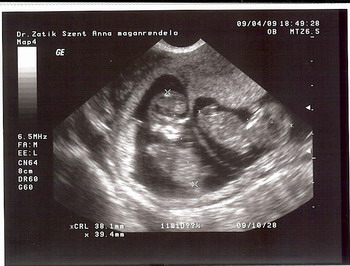

Este UH Dr Zatik Jánosnál (szimpi doki). Mindkét drágánk 38 mm-es, 11 hetes + 1 naposnak felelnek meg, szal szép nagyok. És az egyik integetett nekünk meg vizibiciklizett. :) A másik is eleven volt egy pár percig, de aztán megszeppent a "kamerától", és befordult. :lol:

Kép

rana!nagyon jó a kép a kicsikről!!!!!gartulálok!egyébként tényleg szimpi doki Zatik.akkor nála maradsz?vagy még szétnézel úgymond...? :)